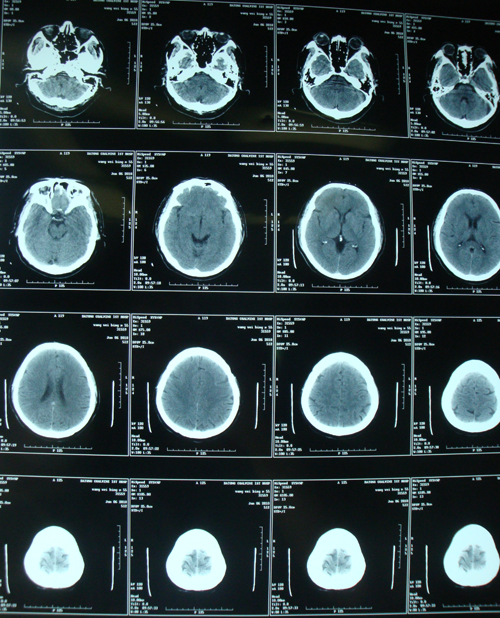

头颅CT:右侧基底节腔隙性脑梗塞

脑梗塞(右侧基底节)